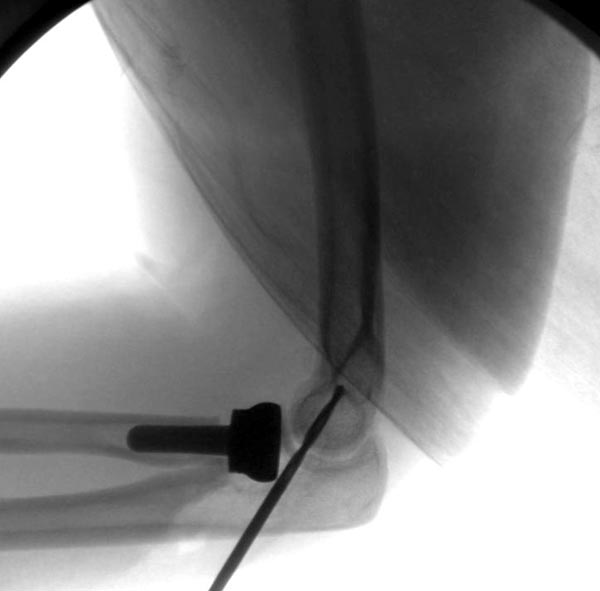

[Ortho] ПЕРЕЛОМ ГОЛОВКИ ЛУЧЕВОЙ КОСТИ.

Второе наблюдение

Вложение не в текстовом формате было извлечено…

Имя     : 2 Elbow radial head fx.JPG

Тип     : image/jpeg